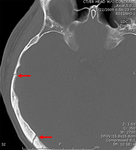

Linear parietal fracture without depression

From the teaching collection of Demetrios Demetriades; used with permission